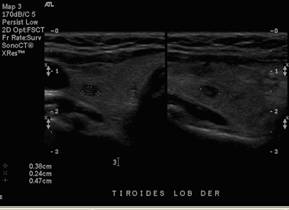

58y/o female with

elevated PTH (293pg/ml) and neck ultrasound that showed two small nodules in the

right thyroid lobule (right hand side)